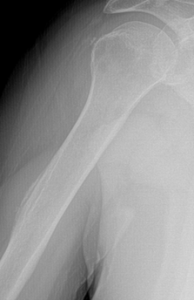

4. Pseudotumor Deltoideus

This normal variant appears as a prominent deltoid tuberosity with cortical radiolucency and irregularity. This finding occurs due to the insertion of the deltoid tendon at the deltoid tuberosity. This non-pathologic anatomic variant can be confused with malignancy, due to the irregular lucent appearance and the simulation of an aggressive periosteal reaction. A knowledge of the classic location and appearance should allow for proper diagnosis and avoidance of unnecessary imaging or biopsy.